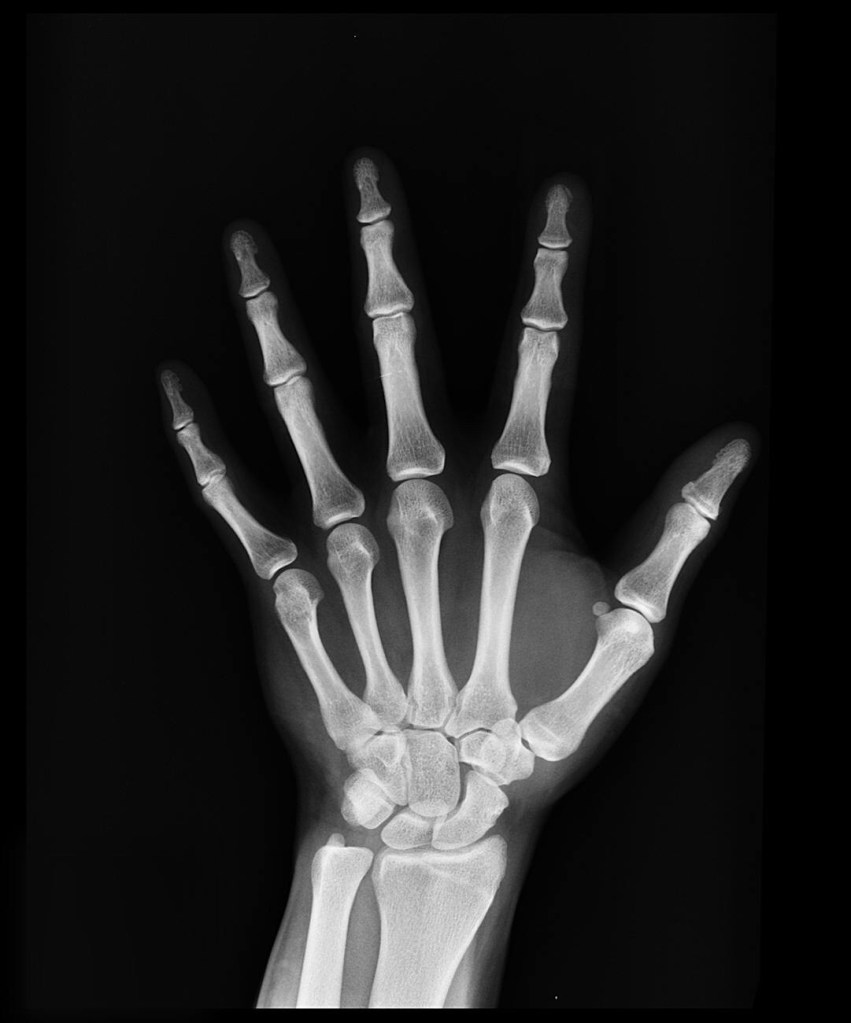

The funny thing about my thumb was that it was sore for a few days before I went to the doctor. Then the x-rays showed a break.